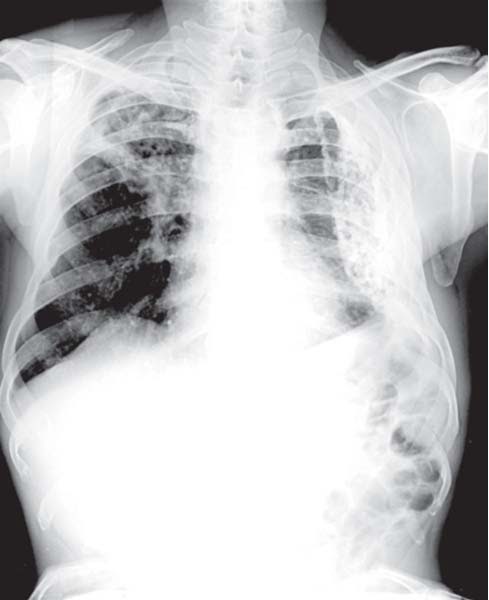

• Pleural Plaques The Cxr Shows Multiple Opacities They Have Irregular Shapes And Do Not

Pleural Plaques The Cxr Shows Multiple Opacities They Have Irregular Shapes And Do Not Parkersburg Mesothelioma Lawsuit

The plaque appears in profile as a sharply marginated dense band of soft tissue ranging from 1 to 10 mm in thickness paralleling the inner margin of the lateral thoracic wall.

The percentages of confirmed pleural plaques on ct scans by type number of confirmed pleural plaque on ctnumber of observed on cxr were 93 4043 for straight 89 5663 for diamond 88 78 for double 83 1923 for tapered medially 80 2025 for parallel 77 2330 for crescent 79 1114 for tenting 72 1825 for tapered. Tap onoff image to showhide findings. Pleural plaques may have a well defined edge.

In 13 of these 76 patients with pleural plaques the original ct scan was performed due to suspicion of prior asbestos exposure. The plaques form in the parietal pleura including that of the mediastinum arrowheads and diaphragm asterisk. Pleural plaques circumscribed areas of hyaline fibrous tissue on the surface of pleura develop in direct response to the presence of fibres are often found as an incidental finding on chest xray.